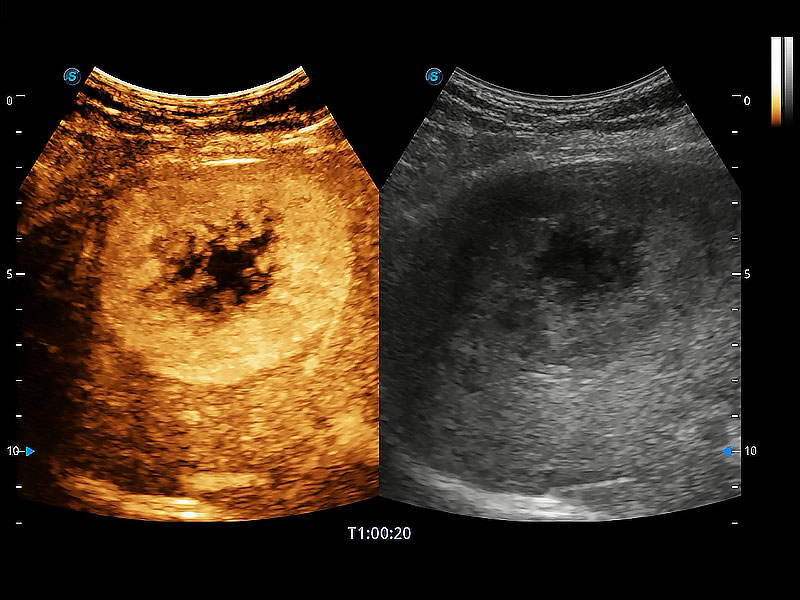

• 全面的造影成像

非线性融合造影成像充分利用谐波和基波信号,为难以观察的血流进行增强显像。可用于线阵、凸阵、微凸阵、相控阵探头。